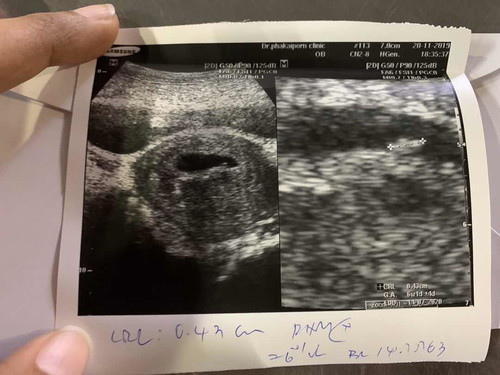

หาตัวเด็กไม่เจอ // เจอถุง2ถุง เป็นถุงเลือดที่อาจจะแท้ง

>>หมอบอกว่า 6 w ตอนแรกซาวหาเด็กไม่เจอ แต่ซูมดูเจอตัวเล็กๆ แบบนี้ปกติมั้ยคะ เล็กเกินไปรึป่าว แต่เจอหัวใจเต้นแล้ว >> และเจอ 2 ถุง แต่อีกถุงเป็นคล้ายๆถุงเลือด หมอถามว่าปวดท้องบ้างมั้ย เราปวดท้องค่อนข้างบ่อย มีสิทธิ์จะแท้ง กังวลมากเลย